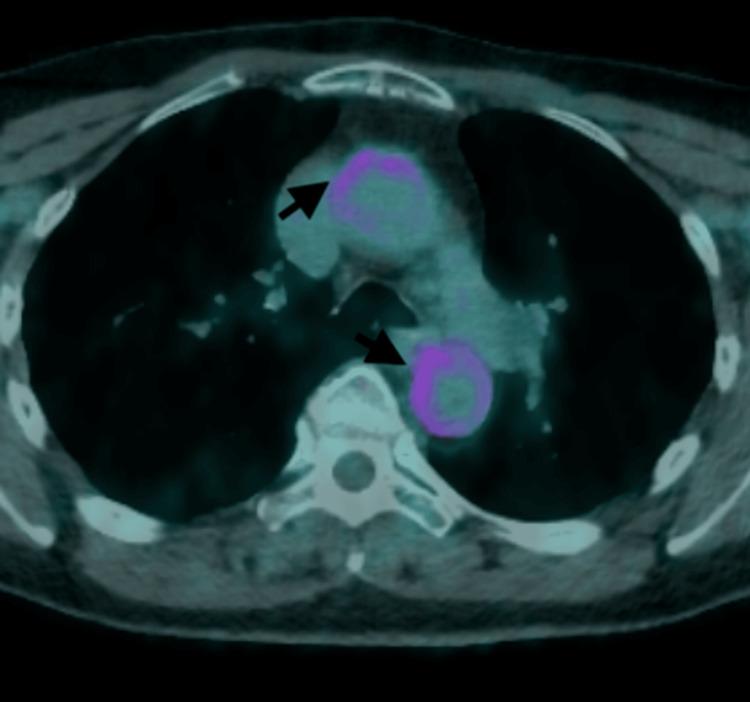

Giant-cell arteritis (GCA) is a type of vasculitis characterised by the presence of granulomas. It is the predominant form of systemic vasculitis in adults and primarily affects the larger arteries in individuals aged ≥ 50 years. GCA affects the major arteries, such as the aorta and its branches, particularly the outer branches of the external carotid artery. Signs and symptoms can be categorised into cranial, extracranial, and systemic manifestations. Patients with headaches, jaw claudication, and vision disturbances usually have extracranial branches of the external carotid artery. Aside from being the prevailing manifestation of GCA, our primary concern regarding this variant is the potential for irreversible vision loss if not properly identified and addressed. Conversely, the GCA can also affect other major blood vessels such as the aorta. Here, we present the case of a 70-year-old Caucasian female patient with cranial GCA who had experienced a temporal headache three years prior. The patient was successfully treated with prednisolone, which was gradually reduced to a very low level with the assistance of methotrexate. Recently, the patient presented with a dry cough that lasted for two months and elevated inflammatory markers. After thorough research, it was determined that there was no evidence of infection, including atypical infections, and that no abnormalities were found in the lungs. Ultimately, via an 18F-fluorodeoxyglucose-positron emission tomography (FDG-PET) scan, the patient was diagnosed with large vessel giant cell arteritis (LV-GCA). This impacted the aorta, carotid arteries, and subclavian arteries. The patient experienced notable improvement in her cough and a reduction in inflammatory markers after receiving a high dosage of oral prednisolone. This case exemplifies the unusual manifestation of LV-GCA and verifies that recurring symptoms may differ from the original presentation. While dry cough is not commonly listed as a symptom of LV-GCA, it can be present as a manifestation or the sole presentation in certain patients, particularly when inflammatory markers are consistently high and there is no pulmonary disease.

巨细胞动脉炎(GCA)是一种以肉芽肿存在为特征的血管炎。它是成人系统性血管炎的主要形式,主要影响年龄≥50岁个体的较大动脉。GCA影响主要动脉,如主动脉及其分支,特别是颈外动脉的外周分支。体征和症状可分为颅内、颅外和全身表现。有头痛、颌部间歇性运动障碍和视力障碍的患者通常累及颈外动脉的颅外分支。除了是GCA的主要表现外,我们对这种变体的主要担忧是,如果未得到正确识别和处理,可能会导致不可逆的视力丧失。相反,GCA也可影响其他主要血管,如主动脉。在此,我们报告一例70岁白种女性颅部GCA患者,该患者三年前曾出现颞部头痛。患者接受泼尼松龙治疗成功,在甲氨蝶呤的辅助下逐渐减至非常低的剂量。最近,该患者出现持续两个月的干咳且炎症标志物升高。经过全面检查,确定没有感染证据,包括非典型感染,肺部也未发现异常。最终,通过18F-氟脱氧葡萄糖正电子发射断层扫描(FDG-PET),该患者被诊断为大血管巨细胞动脉炎(LV-GCA)。病变累及主动脉、颈动脉和锁骨下动脉。该患者在接受高剂量口服泼尼松龙后,咳嗽明显改善,炎症标志物降低。本病例例证了LV-GCA的不寻常表现,并证实复发症状可能与最初表现不同。虽然干咳通常未被列为LV-GCA的症状,但在某些患者中可能作为一种表现或唯一表现出现,特别是当炎症标志物持续升高且无肺部疾病时。